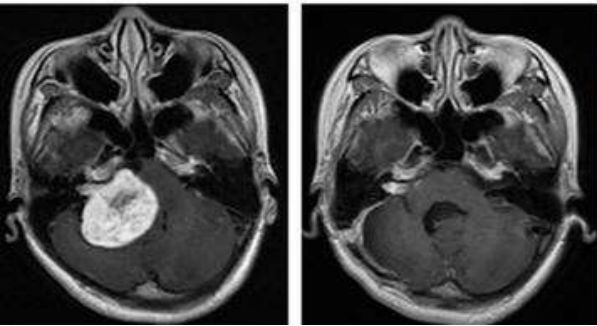

广东的吴女士在2013年7月出现左耳听力下降及左上颈明显肿大淋巴结,本以为是炎症,结果去医院检查后才被确诊为:非角化性癌,分化较差,鼻咽腔肿瘤侵润咽旁和颅底。双侧淋巴结转移。分期为:T3N1M0。

经过多西他赛+铂类化疗联合放疗后,病灶都有了明显的缩小。

不幸的是,2015年2月,复查结果显示,左侧鼻腔壁肿瘤局部复发。因为之前已经接受过了放疗,所以复发后吴女士可选的治疗方案很少。

再经过会诊后,吴女士了解到质子可以治疗复发的肿瘤,于是,吴女士选择了去国外接受质子质子治疗。

治疗期间,吴女士唾液分泌、皮肤、甲状腺无显著影响。治疗后MRI显示鼻咽左侧壁的局部复发已经明显缩小。两个月后吴女士开始正常上班。目前随访,病情处于稳定状态。